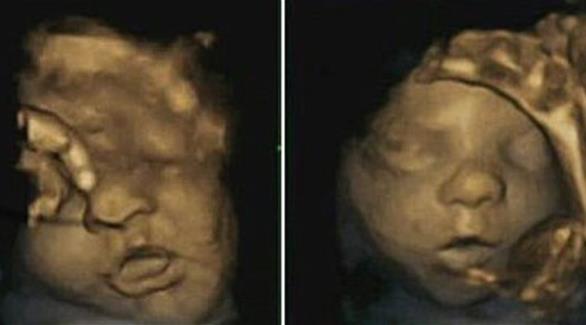

الجنين يتمرن على الابتسام استعداداً للقاء والديه

لندن: كشف باحثون بريطانيون أن الجنين يتمرن على الابتسامة داخل رحم أمه استعداداً للقاء أبويه، وذلك حسبما أظهرت مجموعة من الصور رباعية الأبعاد "4D".

وتوصل الباحثون إلى هذه النتيجة بواسطة هذه الصور رباعية الأبعاد "4D" التي مكنت من تسليط الضوء على تعبيرات وجوه مجموعة الأجنة قبل حدوث الولادة بفترات تصل إلى 16 أسبوعاً.

يذكر أنه تم التقاط هذه الصور رباعية الأبعاد باستخدام أشعة الموجات فوق الصوتية لحوالى 15 جنينا، تتراوح أعمارهم ما بين 24 إلى 36 أسبوعاً من بداية الحمل، بحسب صحيفة اليوم السابع.